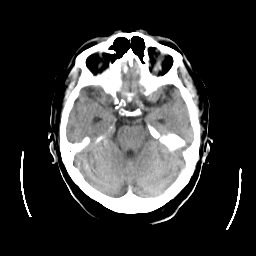

CT Study #2 -- Slice #9